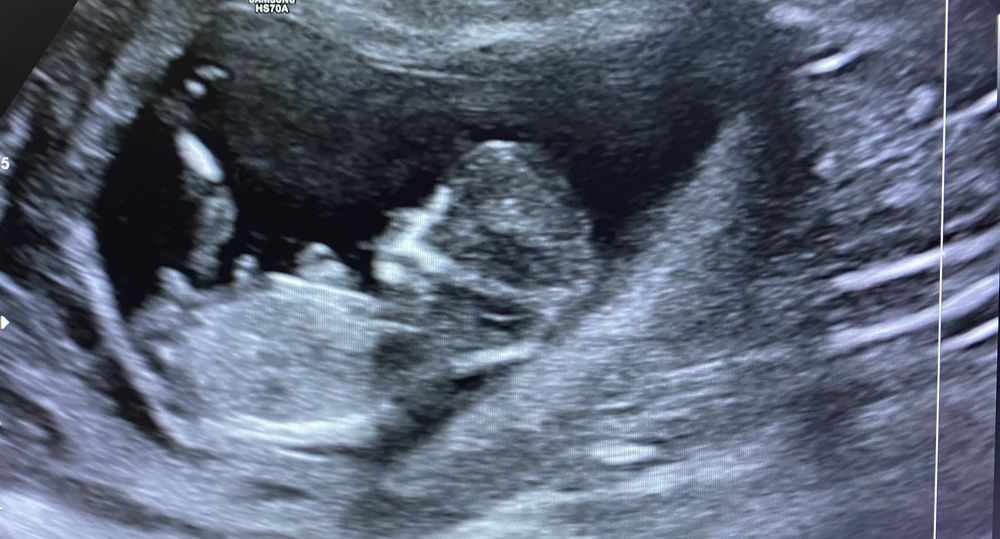

Сегодня был первый скрининг в 12 недель ровно) пол пока не предположили, но тааак интересно) может кто увидит?😁🙈

Неизвестно. То, что так очевидно торчит, совершенно необязательно пацан. Если прям неймется, сдайте в инвитро кровь на пол ребенка и все.

Ой девочки, спасибо всем большое за ответы!))) я тоже чувствую, что там мальчик! Но муж уверяет, что девчонка)😁